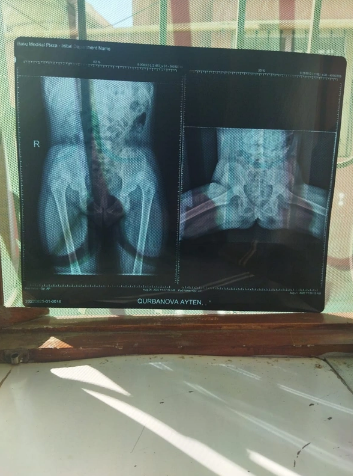

Yeddi yaşlı Qurbanova Aytən Şirin qızı anadangəlmə bud-çanaq oynağının hər iki tərəfli çıxığı xəstəliyindən əziyyət çəkir.

"Aytənin onurğasında lordoz var (anadangəlmə və ya sonradan qazanılmış onurğa əyriliyi, onurğa sütununda bel və omba hissədə olan önə əyrilik. Bu əyriliklər beli şaquli vəziyyətdə tutur, yeriyən, qaçan və tullanan zaman narahatlıq yaradır - red.), əməliyyat olunmalıdır.

Qızımın hər iki bud-çanaq oynağına da implant qoyulmalı idi. Sağ ayağı özəl klinikaların birində əməliyyat edildi. 7 min manat pul ödədik. İndi isə digər ayağı əməliyyat edilməlidir. Bunun üçün də bizə 7 min manat pul lazım idi. Həmin puldan 4800 manatı toplamışıq. Geriyə qalan 2200 manatı xalqımızın dəstəyi ilə toplayacağımıza ümid edirik. Həkim dekabrın 1-i Aytənin digər əməliyyata girməsi üçün vaxt təyin etsə də hələ də pulu toplaya bilməmişik. İmkanlı şəxslərdən balama dəstək olmaqlarını xahiş edirəm"

"Valideynin verdiyi məlumata əsasən övladına "Baku Medical Plaza"da anadangəlmə sağ tərəf bud-çanaq oynağının çıxığı əməliyyatı icra olunub. Yaxın zamanda A.Qurbanovaya sol tərəf bud-çanaq oynağı çıxığı əməliyyatının icra olunması nəzərdə tutulub.

Qeyd edək ki, bu diaqnoz üzrə tibbi xidmətin göstərilməsi Xidmətlər Zərfinə daxildir və TƏBİB-in tabeliyindəki dövlət tibb müəssisələrində həyata keçirilir. Ailəyə Elmi-Tədqiqat Travmatologiya və Ortopediya İnstitutuna müraciət etmək tövsiyə olunub və Agentliyin bu məsələdə dəstək olacağı qeyd olunub. Lakin ailə üzvü imtina edərək əməliyyatın özəl klinikada icra olunmasını istəyib.